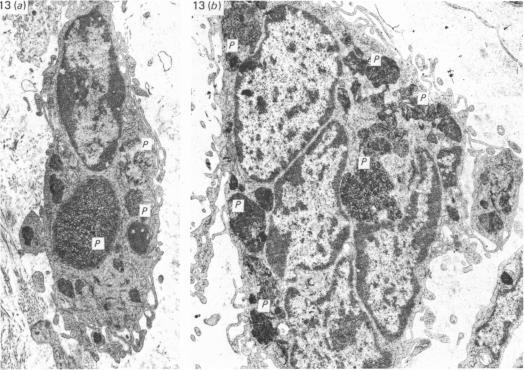

The Harderian glands of rodents manufacture and store porphyrins and are increasingly used as models for porphyrin biosynthesis. Although porphyrins are normally stored as solid intraluminal accretions, interstitial deposits also occur; in the Harderian gland of the female hamster these are found frequently in ovariectomised or aged animals. The present study (employing double-embedding techniques) suggests that interstitial porphyrin deposits are the result of degenerative processes which conform to an escalating pattern. Initially, tubule epithelial and myoepithelial cells become greatly attenuated and there is neutrophil invasion. Secondly, tubule walls disappear leaving previously intraluminal porphyrin stores free within the interstitium. Finally, large interstitial porphyrin accretions become surrounded by foreign body giant cells or are broken down into smaller deposits within free macrophages. These are often associated with plasma cells. Infiltration of the interstitium by lymphocytes may also occur. It may be that the abnormal localisation of porphyrin in the interstitium (i) evokes an immune response and (ii) is related to elevated blood porphyrin levels found in these animals.

啮齿动物的哈德氏腺制造并储存卟啉,越来越多地被用作卟啉生物合成的模型。尽管卟啉通常以腔内固体沉积物的形式储存,但也会出现间质沉积;在雌性仓鼠的哈德氏腺中,这种情况在去卵巢或老龄动物中经常出现。本研究(采用双重包埋技术)表明,间质卟啉沉积是符合递增模式的退行性过程的结果。最初,小管上皮细胞和肌上皮细胞变得极度萎缩,并有中性粒细胞浸润。其次,小管壁消失,使先前腔内的卟啉储存物在间质内游离。最后,大量间质卟啉沉积物被异物巨细胞包围,或在游离巨噬细胞内分解成较小的沉积物。这些通常与浆细胞有关。淋巴细胞也可能浸润间质。间质中卟啉的异常定位可能(i)引发免疫反应,(ii)与这些动物中发现的血卟啉水平升高有关。